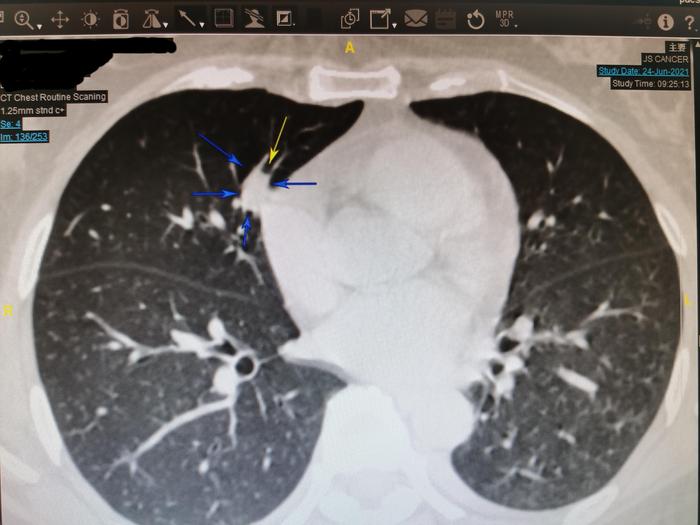

上图,在薄层CT136层面的纵隔窗,同样可见此结节内部局部看起来发暗。

我仔细测量薄层136层面其中一小块发暗的区域,CT值为-54,说明局部有脂肪密度,此实性结节内部有脂肪成分。有脂肪成分的实性肺结节一般是良性肺结节。